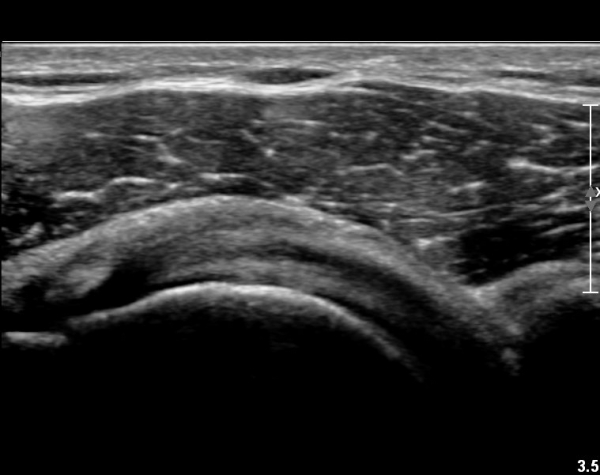

ŽÃËÀÚ¸¦ À§. ¾Æ·¡ ¹æÇâÀ¸·Î µ¹·Á °ß°©ÇϱٰÇÀÇ È¾´Ü¸é°Ë»ç¿¡¼­µµ °ß°©ÇϱٰÇÀÇ

°Ç ½ÇÁú³» ÆÄ¿­ÀÌ °üÂûµÈ´Ù(»çÁø 4, 5).